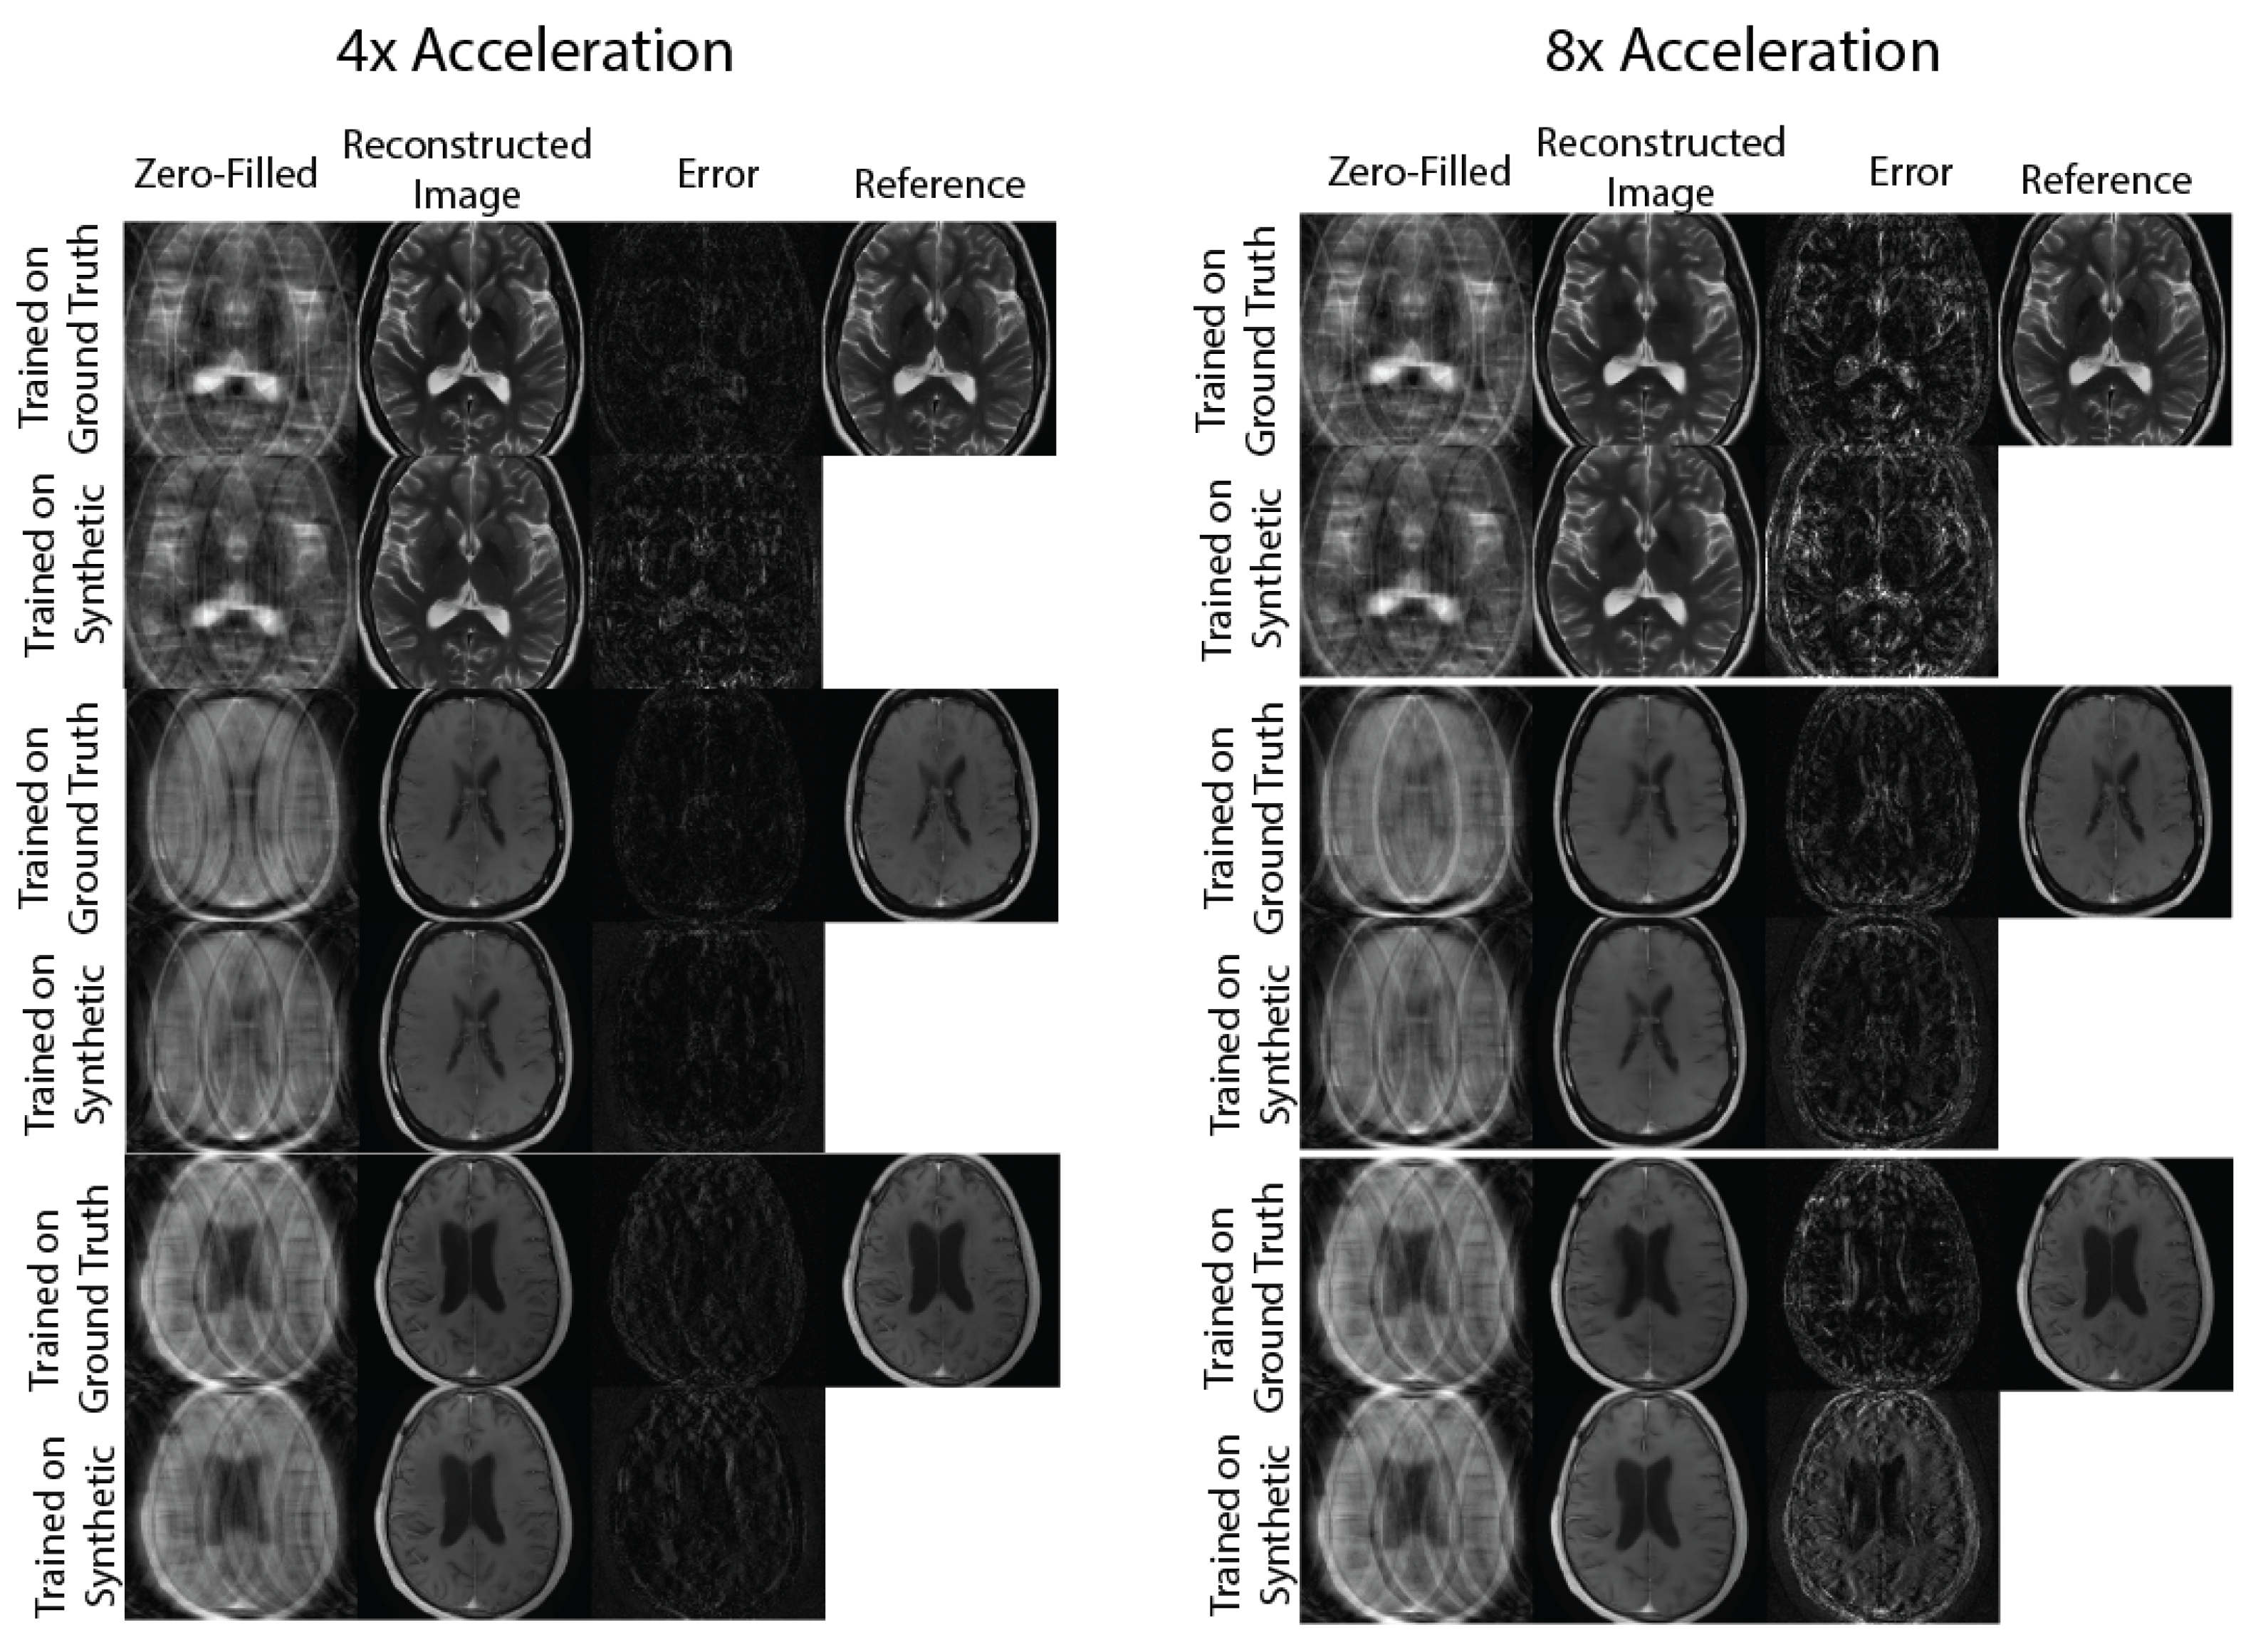

2.4.2. Evaluation: Physics-Based Image Reconstruction

3. Results